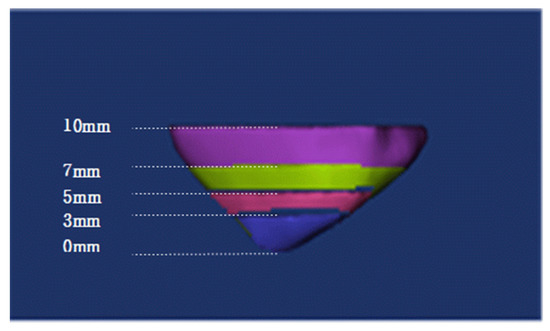

| 3 mm (cm3) | 0.173 ± 0.11 | 0.570 | 0.038 |

| 5 mm | 0.526 ± 0.25 | 1.304 | 0.104 |

| 7 mm | 1.068 ± 0.43 | 2.372 | 0.208 |

| 10 mm | 2.184 ± 0.74 | 4.334 | 0.493 |

| Total | 12.104 ± 4.82 | 25.812 | 0.495 |